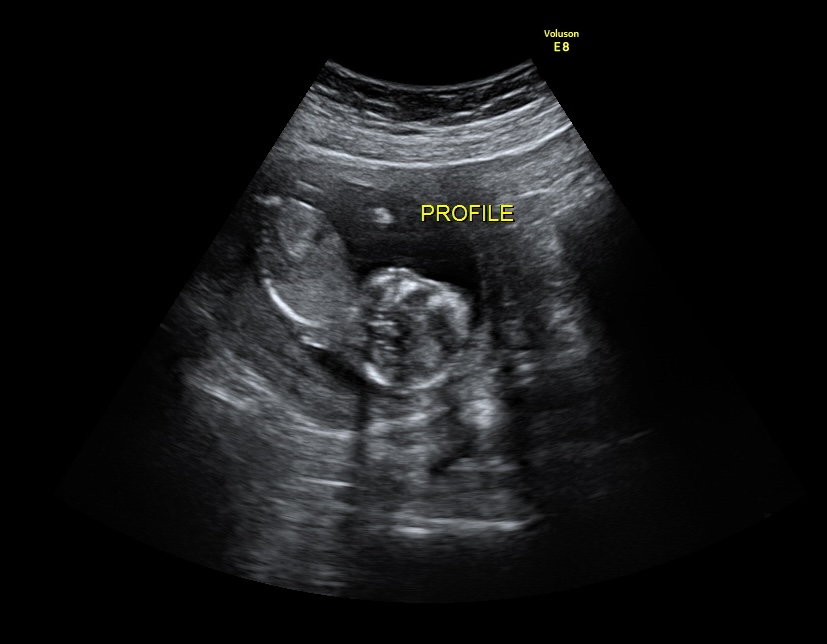

Instead of wondering from week to week whether she was still alive, we went and saw her at the ultrasound studio. She became an active part of our home and our routines. While others pushed through the workweek to reach the weekend, we pushed toward Friday so we could see Millie. We treated those visits like milestones:First day of school photos, first steps, prom pictures, moments we knew we might not otherwise have.

We invited family and friends to join us at our weekly ultrasounds. They met Millie. They loved her. They experienced her life. Today, we have more than 2,000 photos and over 10 hours of video from her time in the womb. Our three-year-old daughter knows her sister because of those ultrasounds. Our family to this day still talks about those visits as some of the most profound experiences of their lives. They were able to love their granddaughter, niece, or cousin in a way they feared they might not get to. Instead of hiding the diagnosis or letting it become something whispered about, we chose to share her openly. It changed the narrative. Millie was not just a diagnosis. She was our daughter.

We specialize in providing elective ultrasounds at no cost to the family. That may look like weekly visits, monthly visits, or even just one meaningful appointment. For many families, those ultrasounds become something to look forward to. They allow parents, siblings, grandparents, and friends to see the baby, bond with them, and build memories while there is still time. We also provide thoughtful gifts and keepsakes that honor each child’s life.